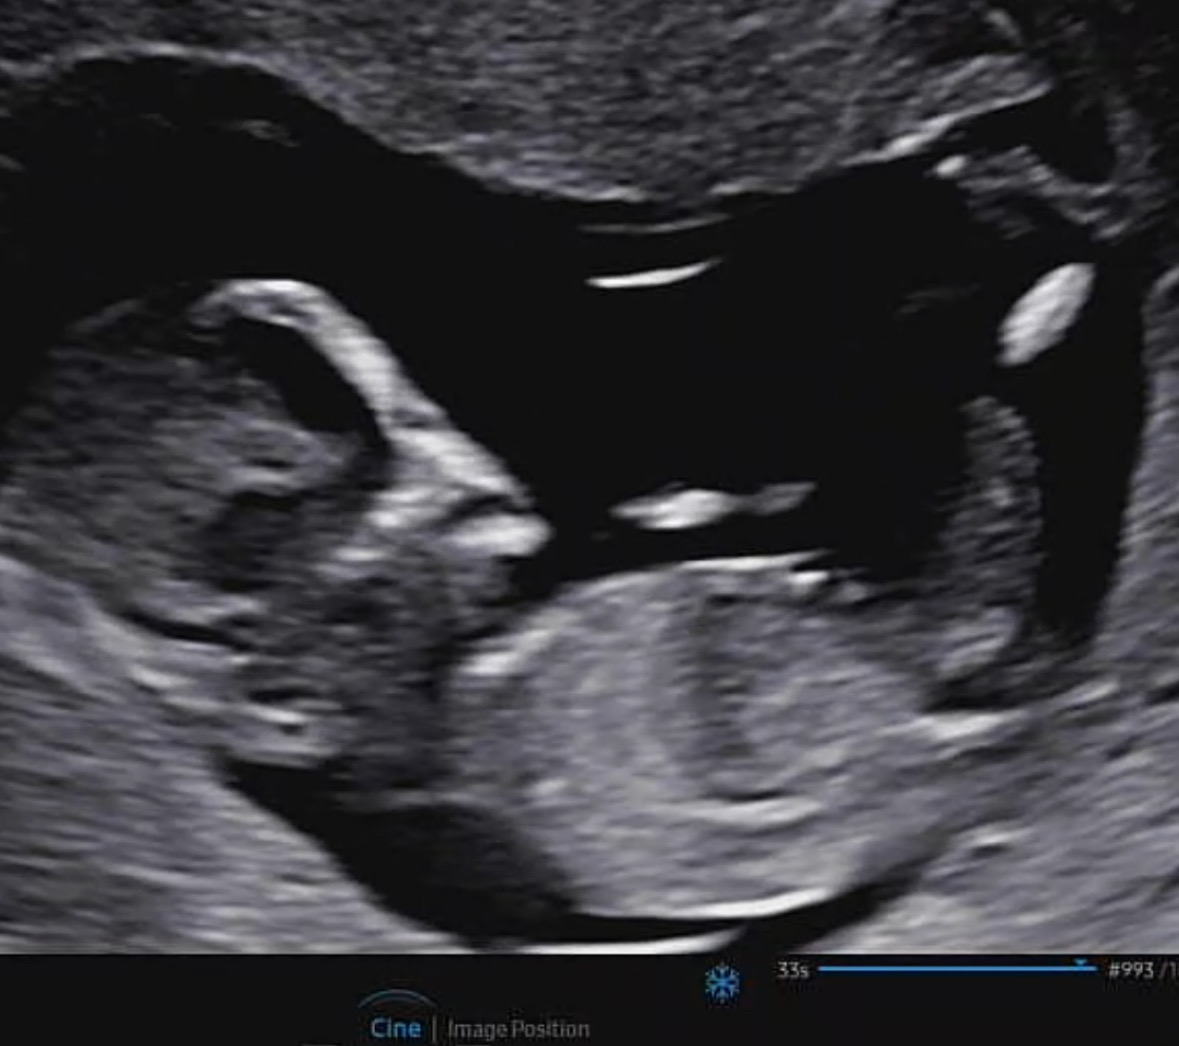

각도법 고수님들 한 번 봐주세요!

12주3일차 초음파입니다!